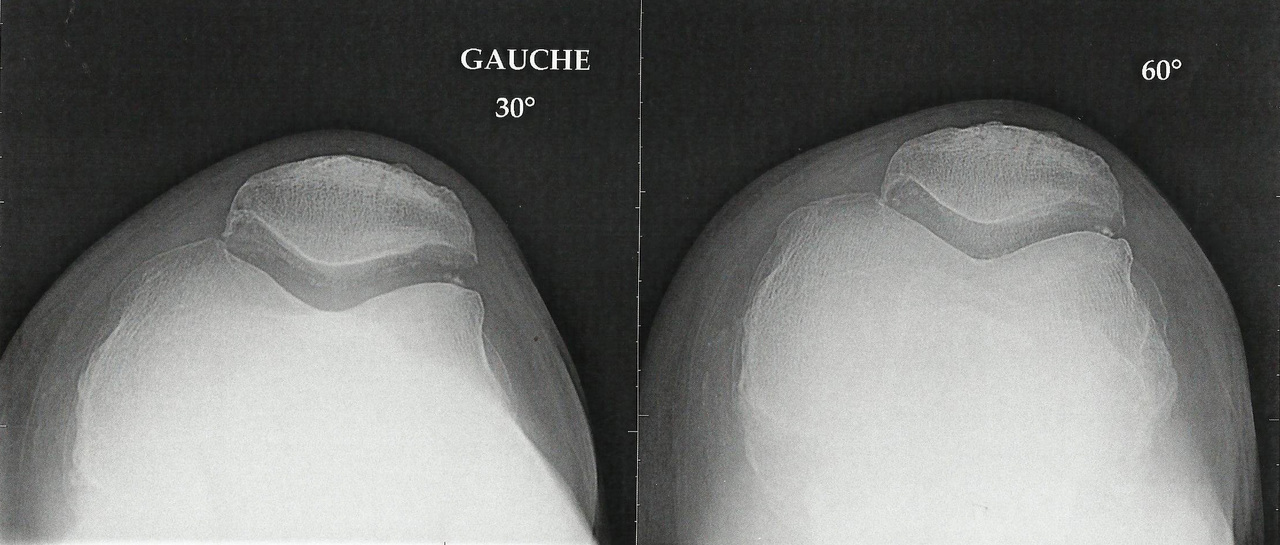

Collection P. Frances La radiographie met en évidence un genu varum, une importante gonarthrose fémoro-patellaire et un fin liseré calcique témoignant d’une chondrocalcinose articulaire.